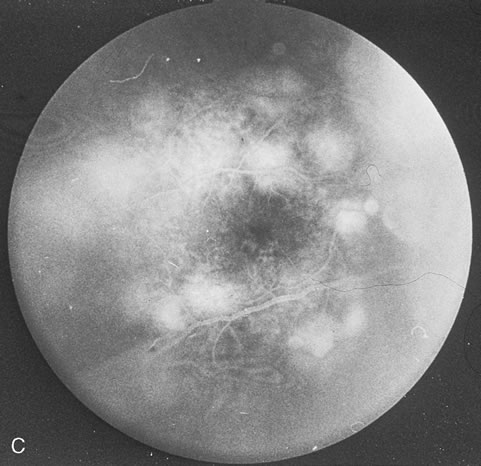

CMV retinitis is common in patients with AIDS. Perivascular granular white or yellowish infiltrates with hemorrhage are typical (Fig. 7). Minimal vitritis or anterior uveitis may be present. The posterior pole, including optic nerve, or peripheral retina may be involved. Optic neuritis may be retrobulbar. Resolution of retinal lesions reveals local retinal atrophy and pigment dispersion. Iridocyclitis may occur secondary to infection of ciliary processes. CMV retinitis in patients with AIDS is considered a poor prognostic sign in terms of life expectancy. Congenital CMV infection may also cause retinitis, as well as anterior uveitis, cataract, and optic atrophy. New foci of retinochoroiditis can develop in later years of congenital infection, and such infants require periodic reexamination as long as virus is shed in the urine.

Pneumocystis carinii pneumonia once was the most common presentation of AIDS. It is typically of insidious onset, with features including dry cough, dyspnea, and a diffuse bilateral interstitial infiltrate evident on a chest roentgenogram. Typical multifocal fundus lesions have been described. They are yellow-white and have a characteristic pattern on fluorescein angiography (Fig. 10A, 10B, and 10C). Diagnosis is made by demonstrating the protozoon via sputum induction, bronchioalveolar lavage, and transbronchial or open-lung biopsies. Treatment modalities include trimethoprim-sulfamethoxazole (TMP-SMX).31